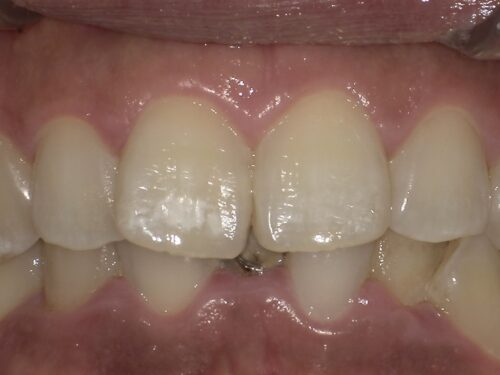

こちらの患者さんは、

前歯のホワイトスポットが気になる、治したいというご希望がありました。

この赤マルで囲った部分にホワイトスポットを認めます。

痛みはなく、審美的な改善をご希望されておりました。